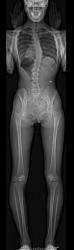

脊柱側弯症とは、左の画像のように正面から見た時に側方に曲がり(側弯)、さらに椎体のねじれ(回旋)が伴う状態です。

側弯症になると、片側の肋骨がコブ状になったり、左右の肩や肩甲骨の高さの違いが目立ったり、ウエストラインが非対称になったりします。